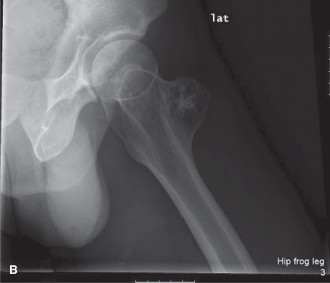

Initial imaging included standard anteroposterior and lateral plain radiographs of the left femur and knee. The radiographs revealed a large, lytic lesion centered within the metadiaphyseal region of the distal femur. The lesion demonstrated an aggressive radiographic appearance characterized by ill-defined margins and a wide zone of transition. Significant endosteal scalloping was present, accompanied by frank cortical destruction, particularly localized to the lateral cortex.

Within the radiolucent matrix of the lesion, areas of faint, irregular calcification were clearly identified. These calcifications exhibited the classic "rings and arcs" and "flocculent" morphology, which is highly pathognomonic for a chondroid matrix. A patchy and discontinuous periosteal reaction was observed, indicative of a biological process that is expanding rapidly enough to outpace the periosteum's ability to lay down mature reactive bone. While severe cortical thinning and erosion were evident, no complete pathological fracture was identified.